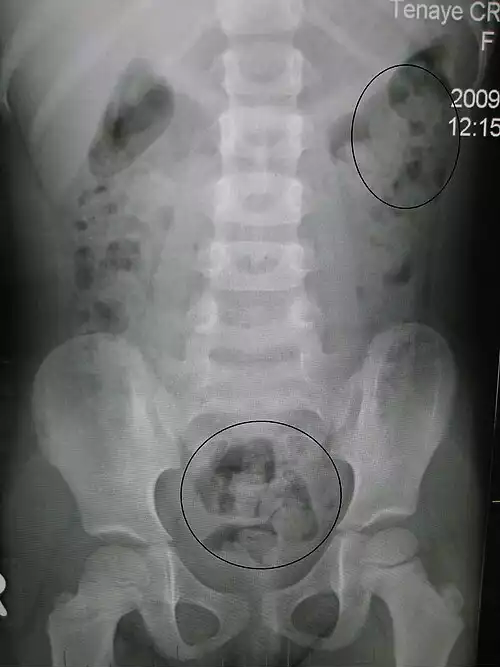

یبوست یا خشکیِ مزاج عارضه ای در دستگاه گوارش است که بر اثر آن، مواد دفعی در رودهٔ بزرگ سفت می شوند و دفع آن ها با درد و سختی همراه می شود. یبوستِ حاد ممکن است سبب بسته شدن روده شود، که به نوبهٔ خود حتی ممکن است نیاز به عمل جراحی داشته باشد. علل بروز این عارضه ممکن است رژیم غذایی نامناسب، برهم خوردن تعادل هورمونی، اثر جانبی داروهای مصرفی یا آناتومی بدن باشد. روش های درمان شامل اصلاح رژیم غذایی و تمرینات ورزشی است.

علت اصلی معمولاً کندی سرعت عبور مواد از کولون یا اختلال دفع است. برخی بیماری ها موجب یبوست می شوند، مانند رژیم کم فیبر یا کم آبی بدن، کم کاری تیروئید، بیماری دیابت، تومورها و سرطان های روده. هنگامی که غذا وارد روده می شود آب و مواد مغذی از آن جدا می شوند و مواد زائد به صورت مدفوع باقی می مانند و به وسیلهٔ انقباض ماهیچه ها در روده حرکت می کند. مصرف کمِ فیبر و آب و نداشتن فعالیت بدنی و جلوگیری از دفع، این امر را دشوار می کند. از دیگر عواملی که منجر به یبوست می شوند می توان به چاقی، استرس، عدم تحرک کافی در روز، کهولت سن، خواب نامناسب و اعتیاد و بارداری اشاره کرد.